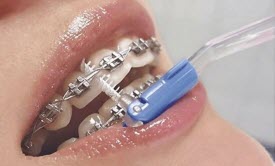

Как ускорить выравнивание зубов? Регулярные визиты без переносов и неявок, соблюдение предписаний врача, правильная гигиена и аккуратное отношение к аппаратам — напрямую влияют на скорость и качество результата. Пропуски, поломки или пренебрежение правилами всегда удлиняют лечение.

Игнорирование гигиены

Воспаление дёсен = тормоз в лечении. Врач не будет двигать зубы на воспаленных тканях и может вообще приостановить коррекцию — снять вам брекеты, пока воспаление не уйдёт. И это только один из самых очевидных примеров того, как соблюдение рекомендаций влияет на срок лечения прикуса.

- Следите за гигиеной.